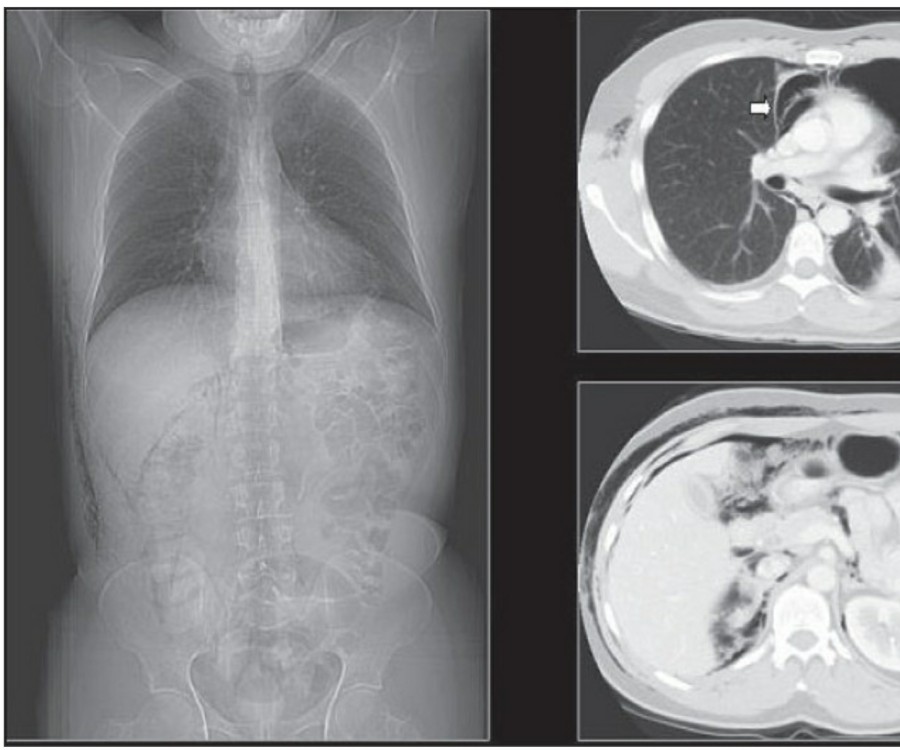

The Normal Chest X-ray중환자실에서 일반적으로 PA chest X ray는 거의 시행하지 않으며, 주로 AP(anteroposterior) chest X ray를 시행한다. AP CXR은 upright position에서 최대 흡기 시 patient-to-x-ray plate가 72inches(182.88cm

방사선 소견상 Pleural effusion은 환자 흉부의 dependent area에 고인다. Erect position에서 확인하기가 쉬운데, 폐의 base에 고임으로써 costophrenic angle blunting을 보이고 lower lobe vessel들의 흐리게 한다. Supine position에서는 확인이 더 어려운데, pleural fluid는 posterior basilar space에 고여서 폐 base 쪽으로 intensity가 증가하는 homogenous density를 보인다. 정상적인 bronchoalveolar marking은 이와 같은 veil-like density 안에서 확인 가능하다. Fluid 양이 늘어나면서 diaphragm의 윤곽이 흐릿해지고 costophrenic angle도 없어지는데, 이 costophrenic angle blunting이 없더라도 pleural space에 1L 정도의 pleural fluid가 있을 수 있다는 것을 기억해야 한다. 그 양이 더욱 늘어날 수록 fluid는 lung의 apex에서 pleural cap으로 나타날 수 있으며, 이는 supine position에서도 확인 가능하다. Pleural fluid는 lung의 medial side에 고일 수도 있으며 이는 mediastinum의 확장으로 보일 수도 있다.

적은 양의 pleural fluid는 꼼꼼히 확인하더라도 supine radiograph에서 놓칠 수 있는데, 만약 chest X ray에서 보이지 않지만 임상적으로 의심이 되는 경우에는 lateral decubitus film으로 확인해 볼 수 있다. Fluid는 dependent position에 고이므로 환자를 의심되는 방향으로 옆으로 눕혀야 한다. Lateral decubitus film은 적은 양의 pleural fluiid는 물론이고 loculated effusion과 free effusion을 확진하는 데도 도움이 된다. 특히 loculated effusion은 한 개 이상의 drain이 필요할 수 있으므로 pleural drainage를 고려할 때 특히 중요한 검사이다. 중환자에서 흔하게 나타나는 subplumonic effusion은 lung base에 존재하는 pleural effusion을 말하는데, chest X ray 상에서 raised hemidiaphragm with flattening and lateral displacement of the dome 형태로 나타나며, lateral decubitus film이 도움이 된다.

Loculated pleural effusion의 진단은 쉽지 않은데, 특히 fissure 안에 있을 때 어렵다. Loculted effusion이 minor fissure 안에 있고 right middle lobe atelectasis가 있다면 supine chest radiograph에서 감별이 어려운데, interlobular effusion은 biconvex edges와 homogenous density로 나타나고 minor fissure는 유지되는 반면, atelectasis는 concave margin과 inhomogenous density로 나타나며 right heart border와 minor fissure가 보이지 않게 된다. 이런 경우 erect lateral radiograph나 CT가 도움이 될 수 있다.